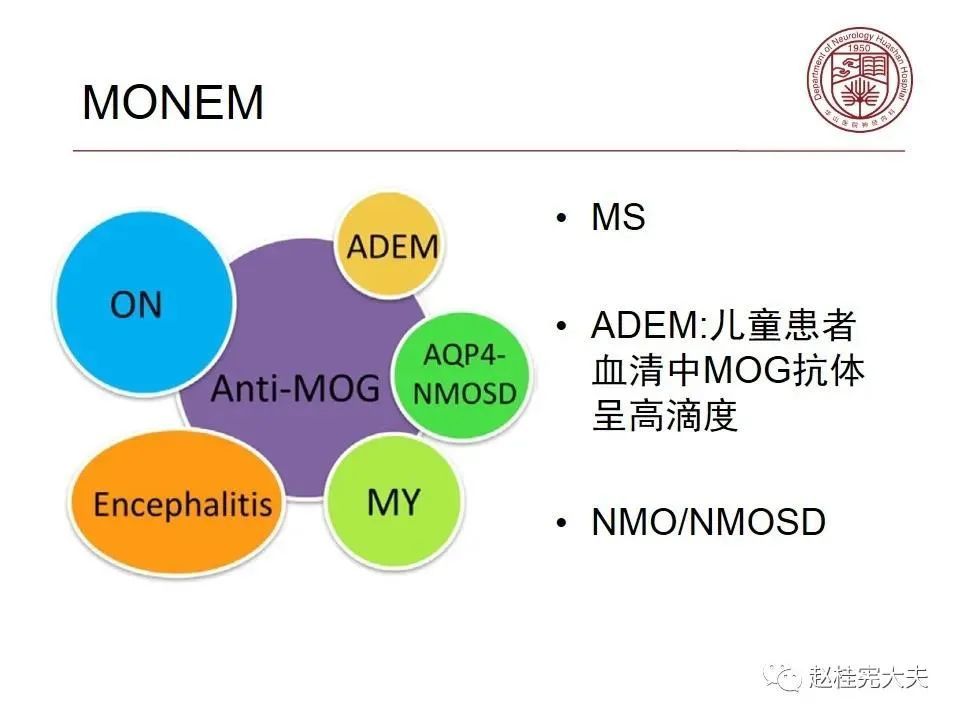

就是一种由MOG抗体介导的中枢神经系统自身免疫性疾病,目前被命名为MOG抗体相关性疾病,即MOGAD,在AQP4抗体未被发现,NMO/NMOSD还没有从MS分离出来时被诊断为MS,当NMO/NMOSD因AQP4抗体的发现从MS分离出后,它被诊断为NMO/NMOSD,在前几年,在一些AQP4抗体阴性的NMOSD患者中发现了MOG抗体阳性,MOG抗体相关性疾病才被认识,曾被命名为MOG脑脊髓炎,终于在2年前正式被命名为MOG抗体相关性疾病,当然,目前还有不少同道还将MOGAD诊断为NMOSD,按照其发病机制和分子靶部位,MOGAD和NMOSD是不同的,应该将其单独列为一个疾病去诊治。(个人意见,欢迎指正和讨论!)